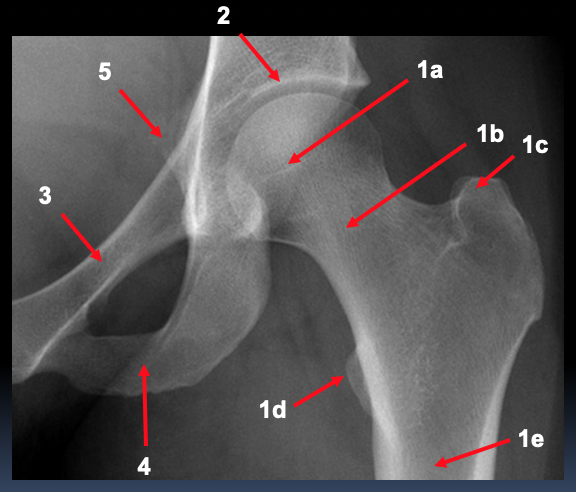

What is represented by 1 in the AP left hip radiograph?

1. femur

a. head

b. neck

c. greater trochanter

d. lesser trochanter

e. shaft

What is shown by 2, 3, 4 and 5 in this AP left hip radiofraph?

What is shown by the arrows on the lateral hip radiograph?

e. proximal shaft

2. acetabulum

3. ischial tuberosity